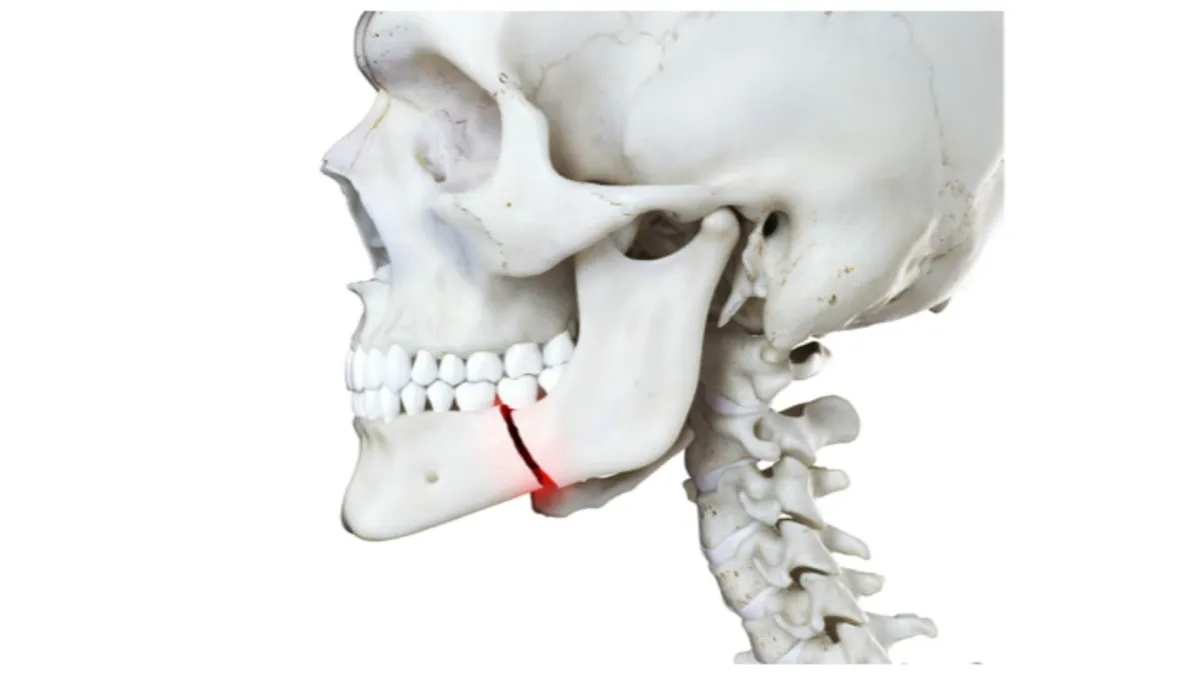

A broken jaw is no fun. Basically, there’s nothing you can do for this other than take some over the counter painkillers and put some ice on it until you can get to the ER. You will likely need a maxillofacial surgeon for this and an surgery as soon as possible.